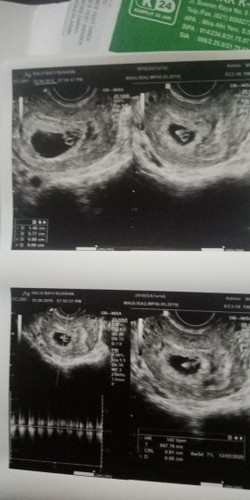

usg krna flek

Kmren aku ngeflek ya allah sampe khawatir bgt mna gda suami d rmh.. Aku lgsg usg d halobayi, td nya aku pkir bakal zonk kyk yg udh2 prnh 2x kguguran dan itu cm kantongnya aja..tp pas kmren usg 7w udh ada janin nya masyaallah djj nya juga normal alhamdulillah ya allah